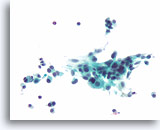

Afbeelding 24

Folliculair neoplasma, hurthleceltype, schildklier FNA, celblok.

Deze afbeelding van de patiënt in afbeelding 23 toont de uniformiteit van de hürthlecelpopulatie die, samen met het robuuste cytoplasma in microfollikels, pleit voor een hürthlecelneoplasma.

40X

Afbeelding 24

Folliculair neoplasma, hurthleceltype, schildklier FNA, celblok.

Deze afbeelding van de patiënt in afbeelding 23 toont de uniformiteit van de hürthlecelpopulatie die, samen met het robuuste cytoplasma in microfollikels, pleit voor een hürthlecelneoplasma.

40X